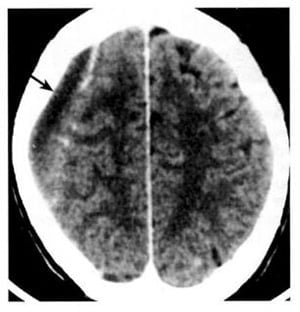

2.8. Máu tụ dưới màng cứng (Hình 1.43, 1.46-48)

Dấu hiệu XQCLĐT:

– Bán cấp (từ vài ngày đến 3 tuần). Mật độ ngang, làm di lệch mặt tiếp giáp chất xám-chất trắng. Sau tiêm, thấy các tĩnh mạch vỏ di lệch vào trong. Màng bên dưới có thể tăng quang.

– Mãn (trên 3 tuần). Khối tụ hình liềm, giới hạn rõ, mật độ thấp, tiếp giáp bản trong hộp sọ. Bắt chất cản quang viền mỏng.

Hình 1.47. Khối máu tụ bán cấp dưới màng cứng có mật độ ngang. Trước tiêm, chỉ thấy hiệu ứng choán chỗ và xóa mất não thất bên bên trái (a). Sau tiêm (b), các tĩnh mạch bề mặt hiện lên (mũi tên) cho thấy rõ hơn ranh giới của khối tụ máu.